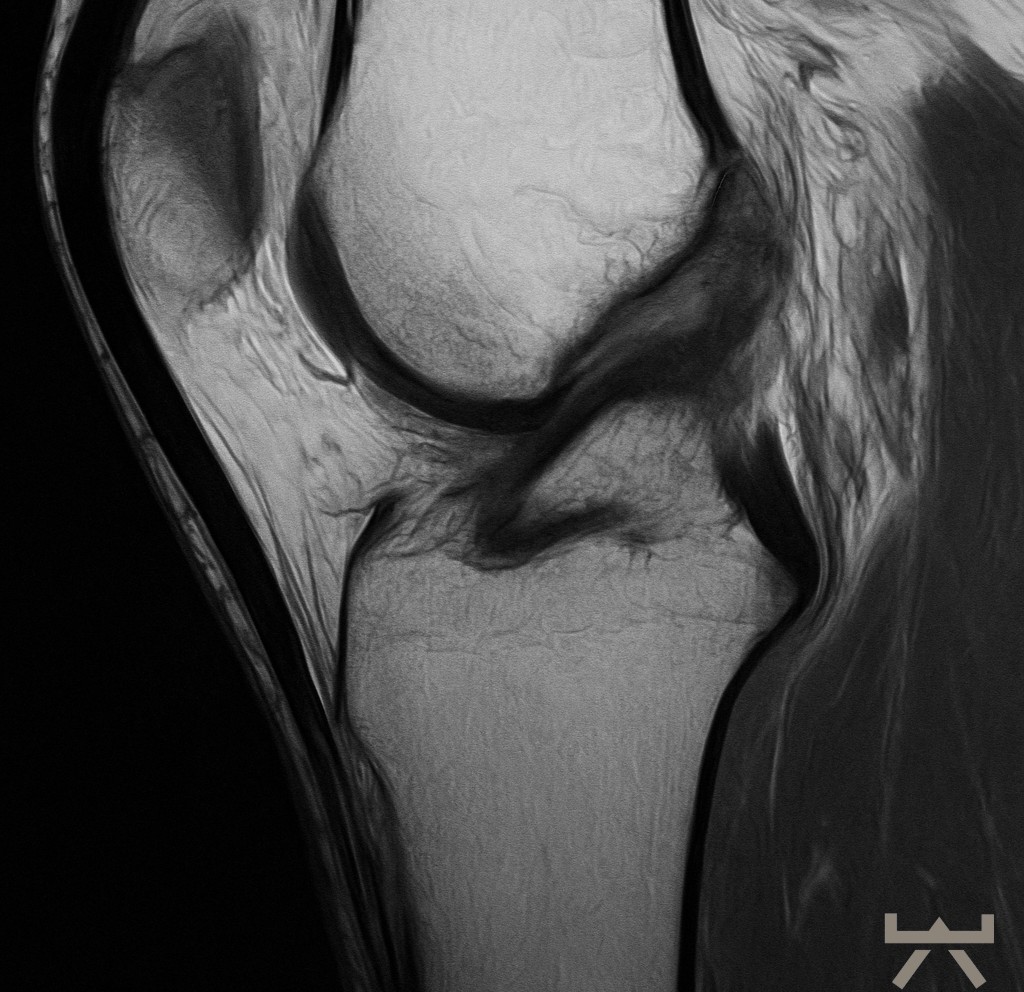

- MRT

- (CT)

Durch die Schwellung ist die Diagnostik in der Bildgebung jedoch erschwert, daher muss diese nach dem Trauma schnellstmöglich erfolgen oder es kann eine wiederholte Untersuchung in der subakuten Phase sinnvoll sein. Hierfür eignen sich die oben aufgelisteten bildgebenden diagnostischen Mittel, wobei das MRT hier die erste Wahl ist. In diesen Untersuchungen werden die nötigen Strukturen des Knies dargestellt. Auch häufige Begleitverletzungen wie Meniskusschäden oder Verletzungen des Außenbandes können in der Magnetresonanztomographie direkt ausgeschlossen/diagnostiziert werden.

Trotzdem muss man berücksichtigen, dass bildhafte Verfahren zur Diagnostik mit Vorsicht zu genießen sind. So müssen nicht alle degenerative bzw. schadhaften Veränderungen von Bedeutung sein, da sie auch normale Alterungsprozesse des Lebens abbilden können. Sowie sich unser Äußeres im Alter verändert (z.B. Falten), verändern sich auch unsere inneren Strukturen im Laufe des Lebens.